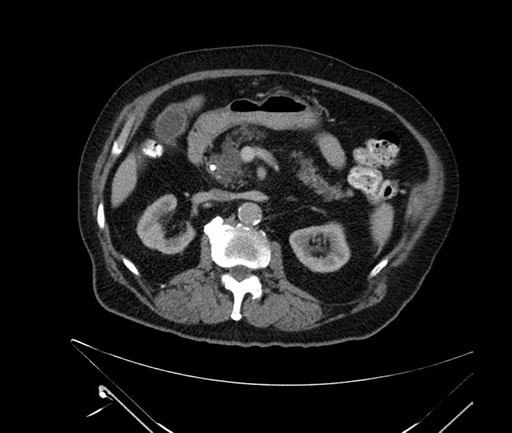

Axial - stented